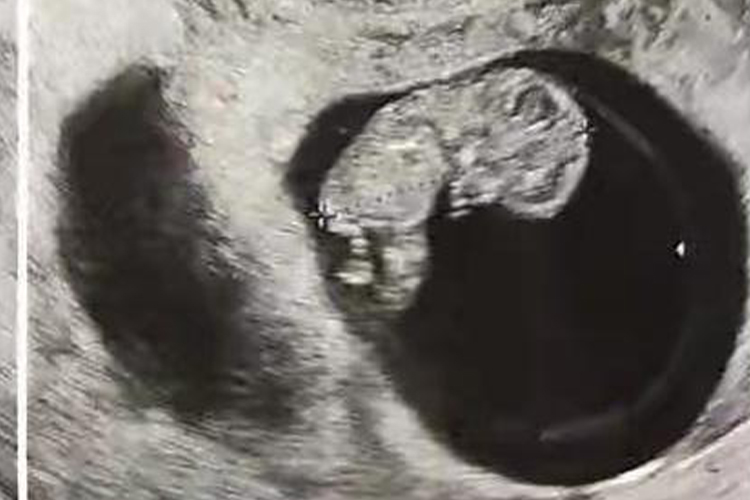

怀孕60天时胚胎已经初具人形,通过腹部B超能够看到胎儿和心脏,以及原始心管搏动。能够看到此时头部约占整个胎体的一半以上,大致能够分辨出四肢。还会出现比较典型的半月形胎盘图像,以及呈扭曲状的带状回声区。